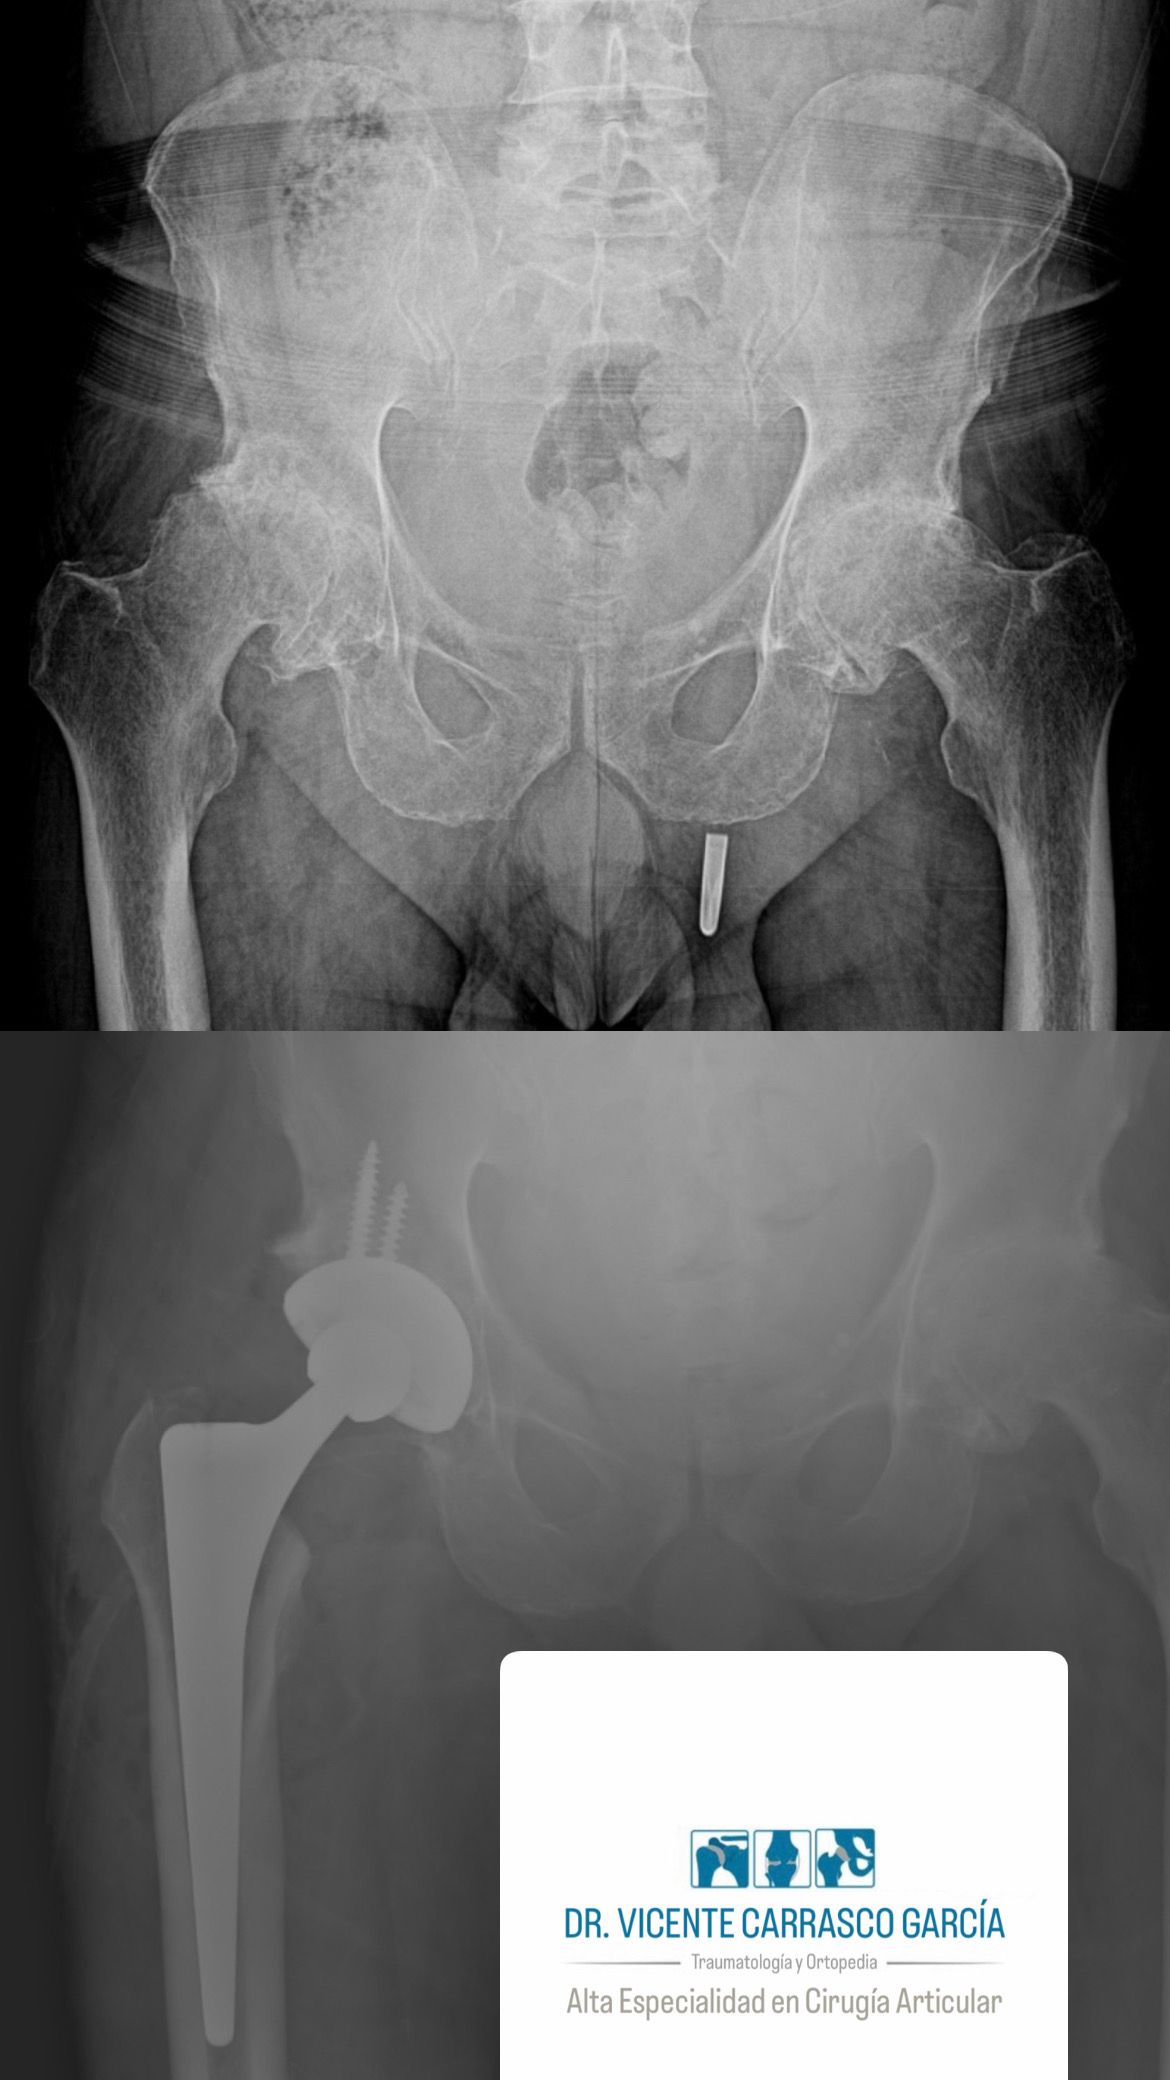

En el último año, he realizado con éxito más de 100 prótesis de rodilla y 100 prótesis de cadera, ayudando a mis pacientes a recuperar su movilidad y mejorar su calidad de vida. Mi objetivo es brindar una atención especializada y personalizada, basada en evidencia científica y en las técnicas más avanzadas disponibles en la actualidad.

• Prótesis de cadera

• Medica Campestre Medical Center Consultorio 205 Artroplastia de la cadera con prótesis total  •

Mi mamá fue operada de la cadera por el doctor y no tengo palabras para agradecerle. Desde el primer momento nos trató con mucha empatía, paciencia y un profundo sentido humano. Nos explicó todo con claridad y nos dio muchísima confianza. La cirugía fue un éxito y hoy, después de meses de dolor e inseguridad, mi mamá volvió a caminar sin molestias, Verla así no tiene precio. Siempre le estaremos agradecidos. Es un médico con un gran corazón y una gran persona yo lo recomiendo mucho.